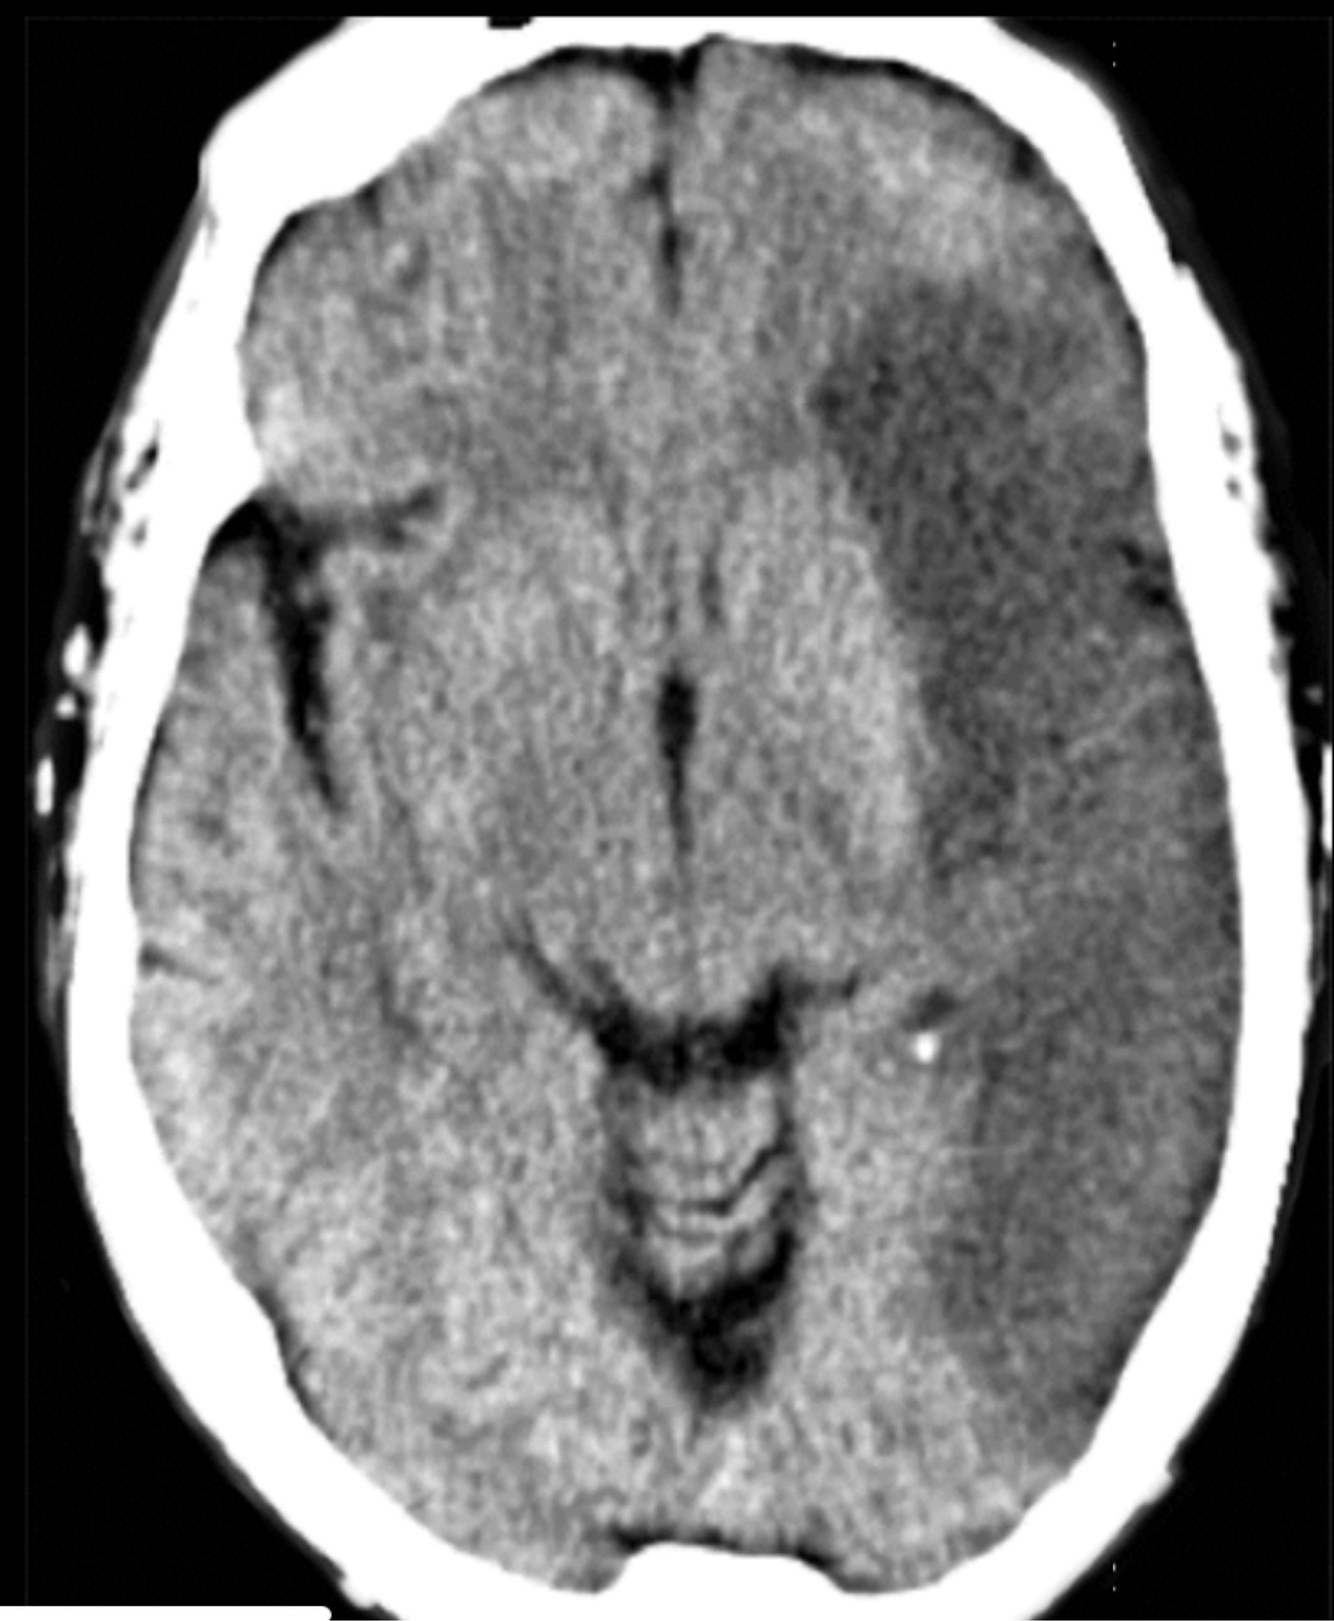

9

Q

A

EVC isquémico agudo